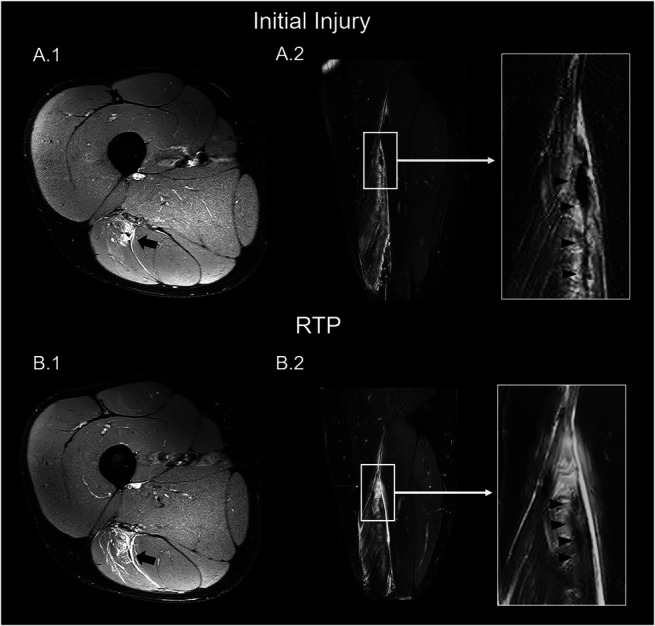

Results: Magnetic resonance images at RTP showed that 55 (95%) participants had intramuscular increased signal intensity (edema) and 44 (76%) participants had intramuscular abnormal low-signal intensity (suggesting fibrosis) on MRI. There was an overall reduction of injury grades according to the modified Peetrons and BAMIC classification at initial injury to RTP. Three (5%) participants had no abnormal signal intensities (grade 0 or grade 0A) on MRI at RTP. Intramuscular tendon disruption, waviness, and tendon thickening were present at RTP in, respectively, 22 (38%), 15 (26%), and 36 (62%). We recorded 3 (5%) reinjuries.

Conclusions: At RTP, 3.0-T MRI shows high percentages of MRI abnormalities (edema, fibrosis, and intramuscular tendon disruption and thickening). We conclude that complete normalization of 3.0-T MRI is not expected for RTP decision after a hamstring injury. Its possible association with reinjury risk has to be determined in larger cohorts.